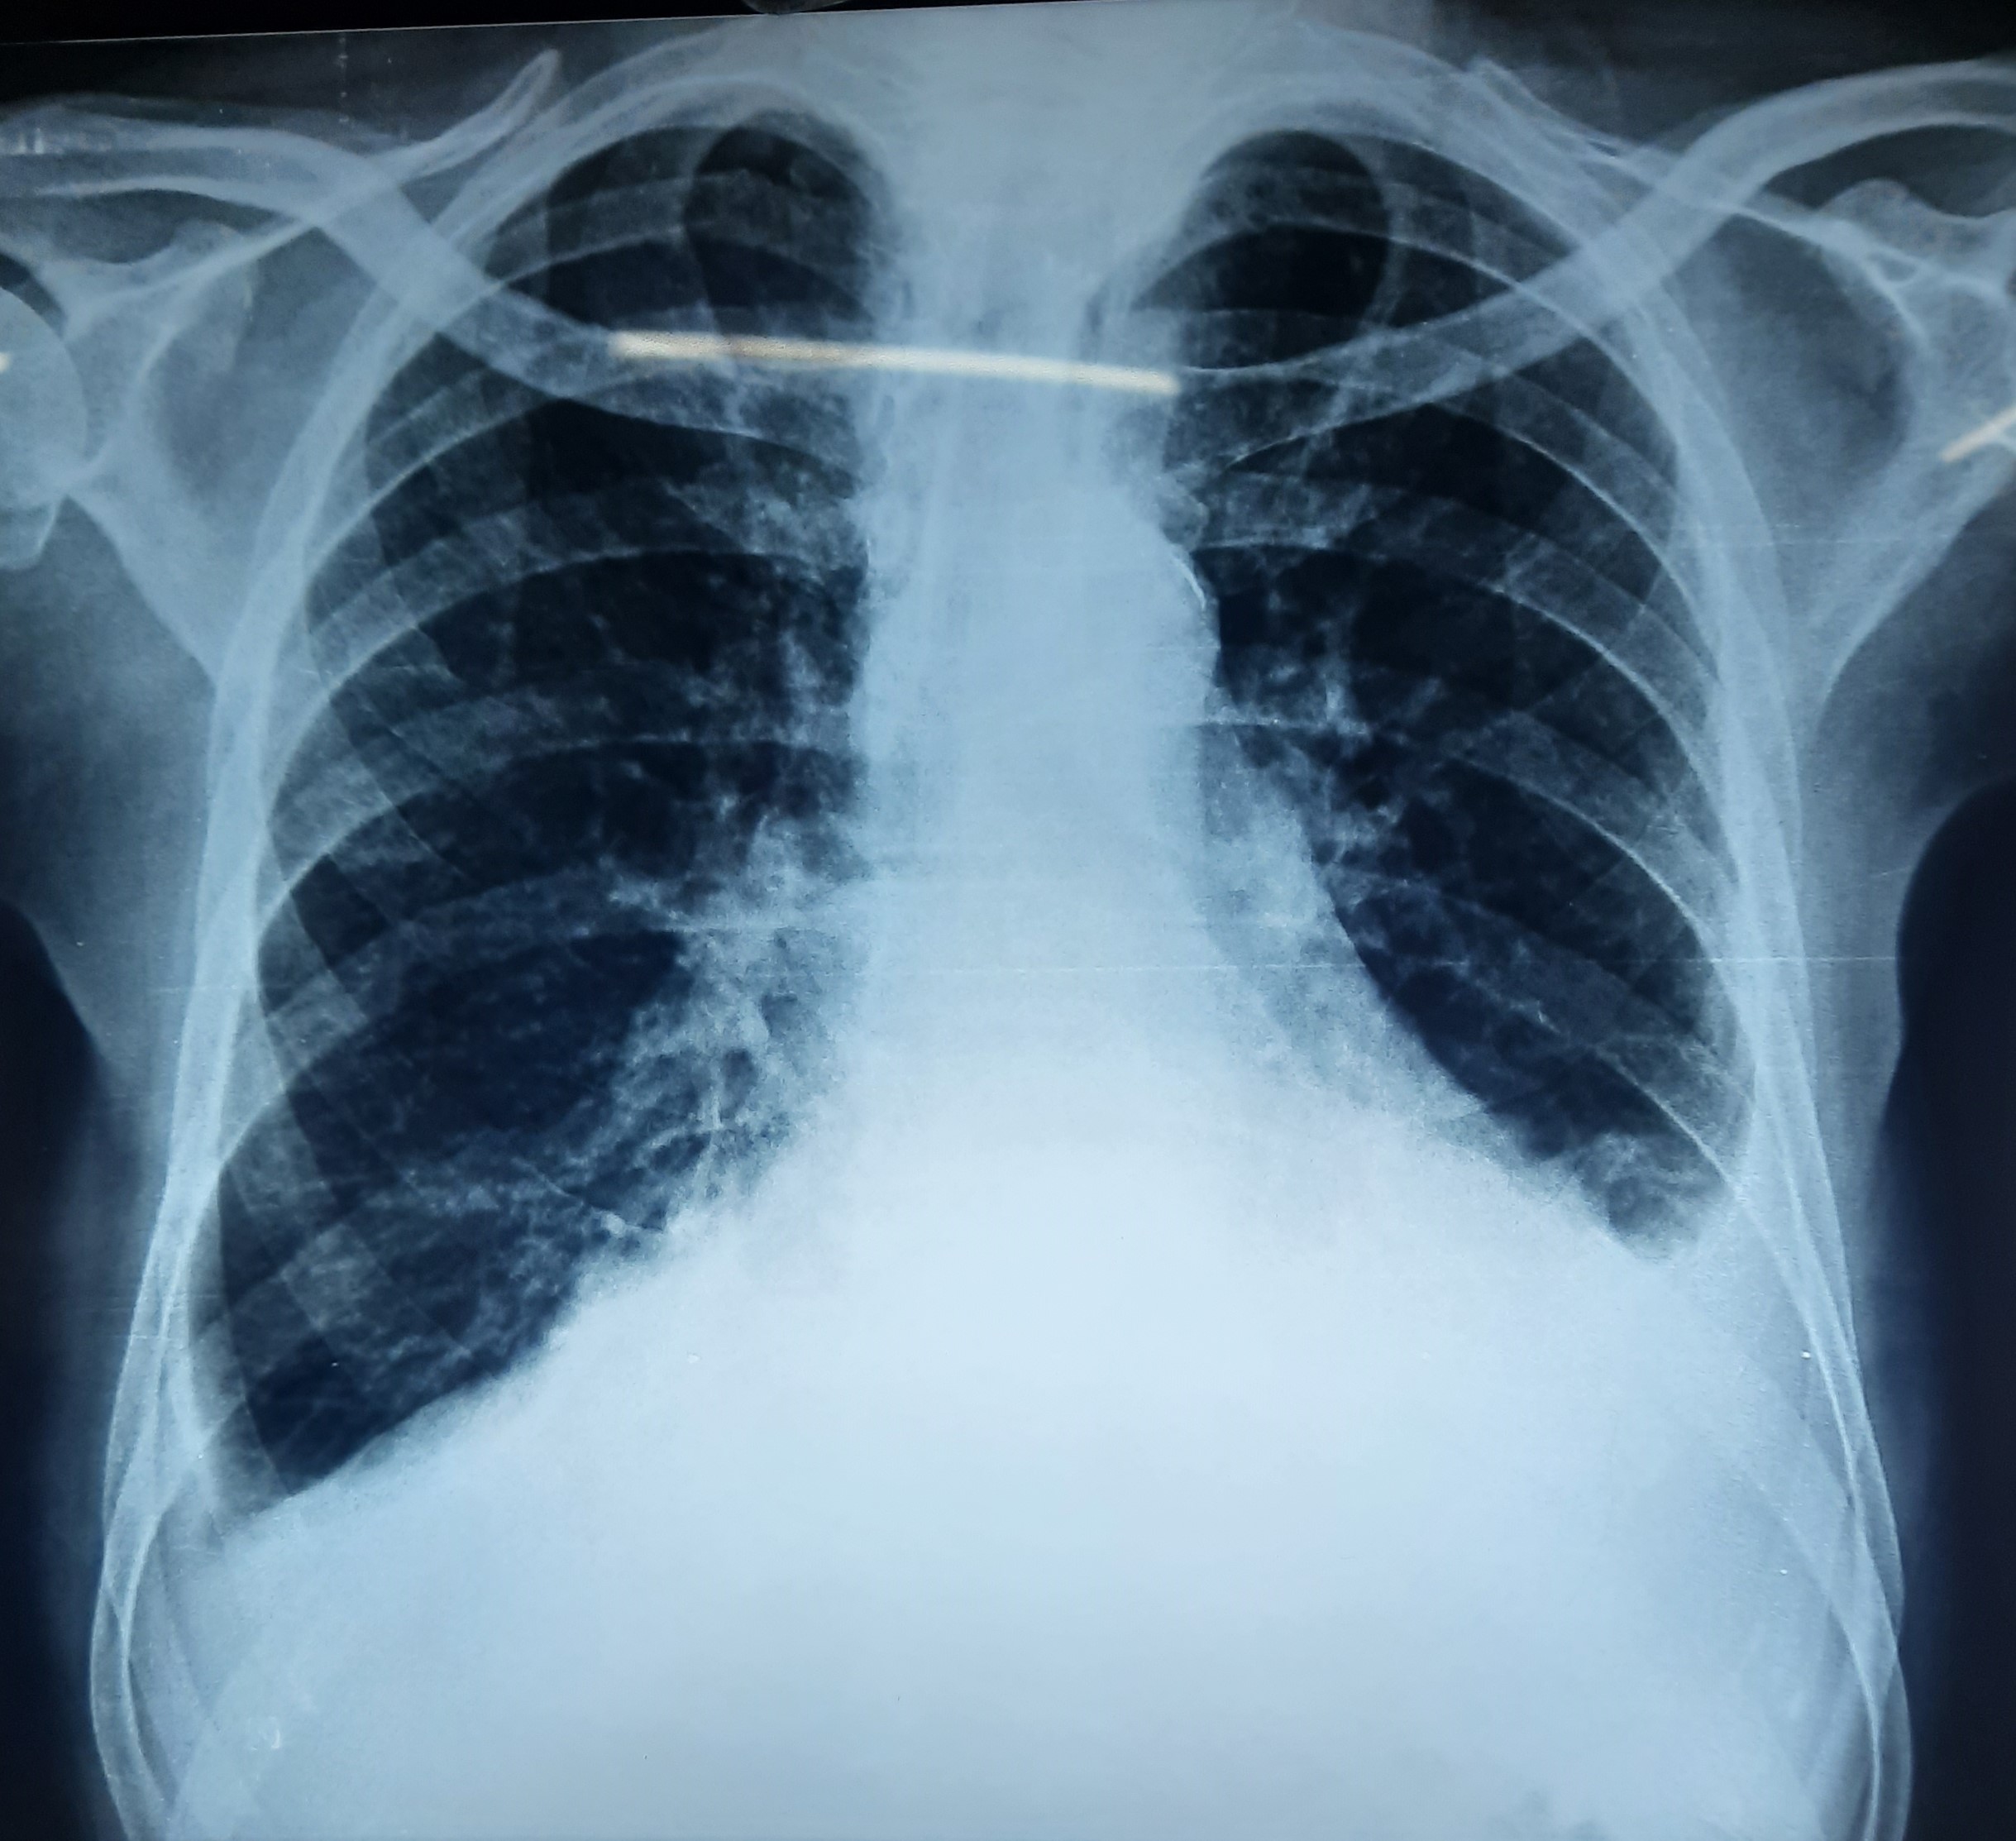

| 197 | IGGMC, Nagpur, Nagpur | P2 | 29-4275 | Meerabai Kuril | Consent taken on Paper | 58 Yrs. |

Provisional Diag : Post TB Bronchiectasis?

Final Diag : Post TB Sequeale (CxR- Bilateral Fibro cavitary Changer) |

Post TB Sequelae | CxR- Bilateral Fibro cavitary Changer | Abnormality visible on x-ray |